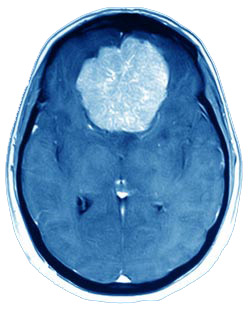

The "ideal treatment" for meningiomas continues to evolve as new technologies give rise to new treatment options. Open surgery has long been regarded as the standard treatment for large or symptomatic meningiomas.

More recently, interest has surged in the use of Gamma Knife Radiosurgery to treat meningiomas. The last decade has seen exponential growth in the number of meningiomas (and other brain tumors) treated with Radiosurgery.

Gamma Knife has proved to be a highly successful treatment for meningiomas. Thousands of patients have been treated worldwide.